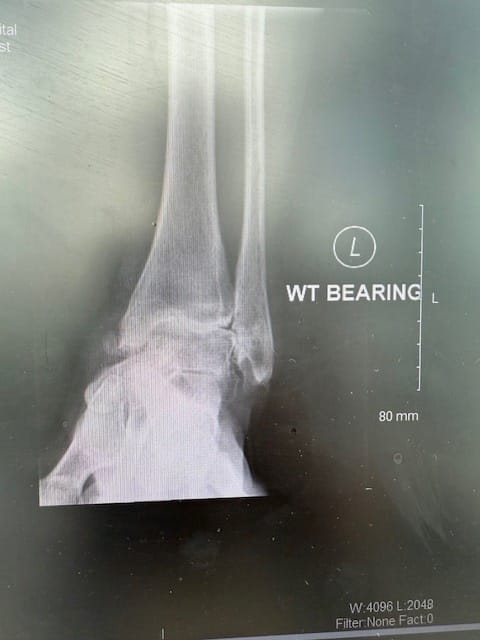

To get further information about her ankle and hindfoot joints we arranged weightbearing X rays which did confirm pronounced osteoarthritis with a varus deformity of both ankle joints, the left again a bit more pronounced than the right. The subtalar and the transverse tarsal joints all looked good.